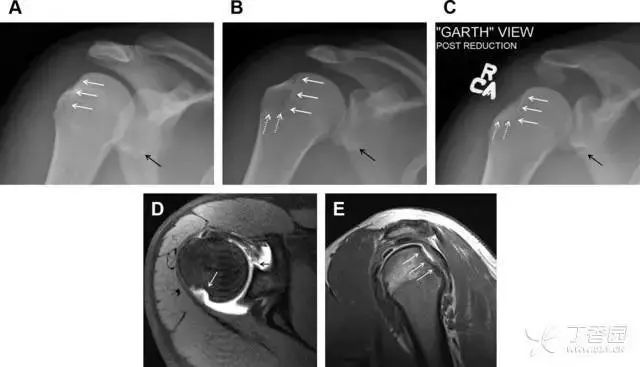

骨折伴盂肱关节不稳

肩关节是最容易脱位的关节之一,肩关节脱位常伴随其它结构的损伤,如血管神经损伤、肩袖损伤、盂唇损伤、Bankart 损伤等。脱位本身诊断往往是明确的,容易被忽略的是其继发的伴随损伤。

需要仔细评估肱骨头、大结节、关节盂边缘、肩峰、喙突等结构。典型的 X 线投射角度包括:内旋位前后位片、外旋位前后位片(Grashey 位)、侧位(肩胛骨 Y 位)、腋位片以及改良腋位片。

图 6 肩关节前脱位伴有 Hill–Sachs 和 Bankart 损伤:(A~C)肱骨头后外侧撞击骨折,白色箭头所示为骨折的内侧边界;(A)内旋位前后位片,(B)「V」形压缩骨折的下边界(虚线短箭头),(C)Garth 位(轴向投影)示 Hill–Sachs 损伤(虚线和实线折箭头),特别是对骨性 Bankart 损伤的诊断有帮助。(D、E)MRI 进一步证实了损伤